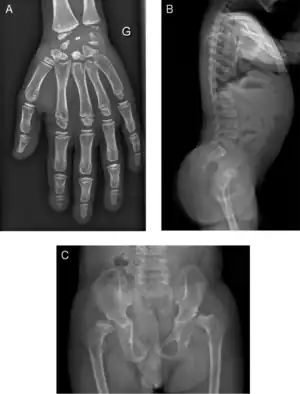

| Radiograph of a WRS child presenting with dysplastic bone growth in various regions of the body. | |

Initially, patients with neonatal or early-childhood onset diabetes are possible candidates for having Wolcott–Rallison syndrome.[1] The other features include multiple epiphyseal dysplasia, osteopenia, intellectual disability, and hepatic and renal dysfunction.[1] Patients having features that suggest Wolcott–Rallison syndrome can be referred for genetics testing. The key way to test for this disease is through genetic testing for EIKF2AK3 mutations.[8] Molecular genetic analysis can be done for the patient and the parents to test for inherited or de novo mutations. It can also show whether the patient's parents are heterozygotes or homozygotes for the normal genotype.[4] X-rays can show bone age in relation to actual age. In typical WRS patients the bone age is a few years less than the chronological age.[4][5][9][10] Hypothyroidism is rare in WRS patients but can occur.[4]